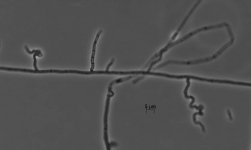

| Species Name: | Nannizziopsis guarroi |

| Taxonomy: | FUNGI Ascomycota, Eurotiomycetes, Onygenales, Onygenaceae |

| Substrate: | amputated leg of bearded dragon (Pogona vitticeps); histopathology + hyphae in many fungal granulomas |

| Characters: | HUMAN/ ANIMAL PATHOGEN deep fungal dermatitis in bearded dragon (Pogona vitticeps) - Bowman MR, Pare JA, Sigler L et al, Med Mycol 45:291-296, 2007 // KERATINOPHILIC digests hairs with penetrating bodies - // MOLECULAR SYSTEMATICS phylogeny of Nannizziopsis and reptile pathogens belonging to the CANV complex - Sigler L, Hambleton S, Pare JA, J Clin Microbiol 51:3338-3357, 2013 (Click for publications citing UAMH 10351) |